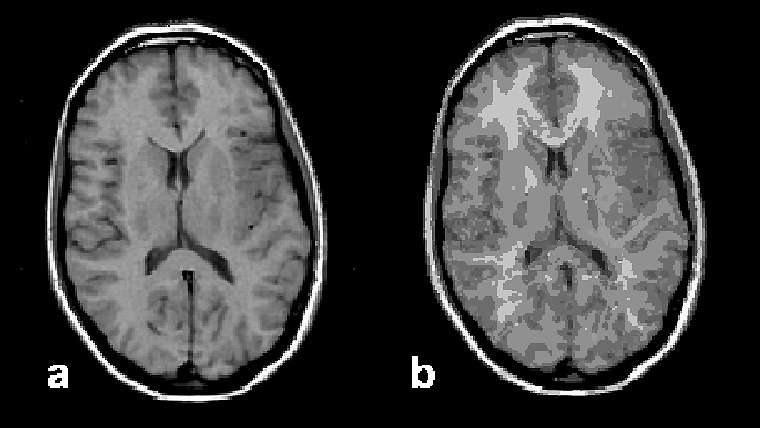

The classical example is gray and white matter separation on the basis of re­la­xa­tion time data (Figure 15-11).

Figura 15-11:

Image segmentation: (a) original brain image, and (b) segmented image presenting 90 different tissue com­­po­nents.